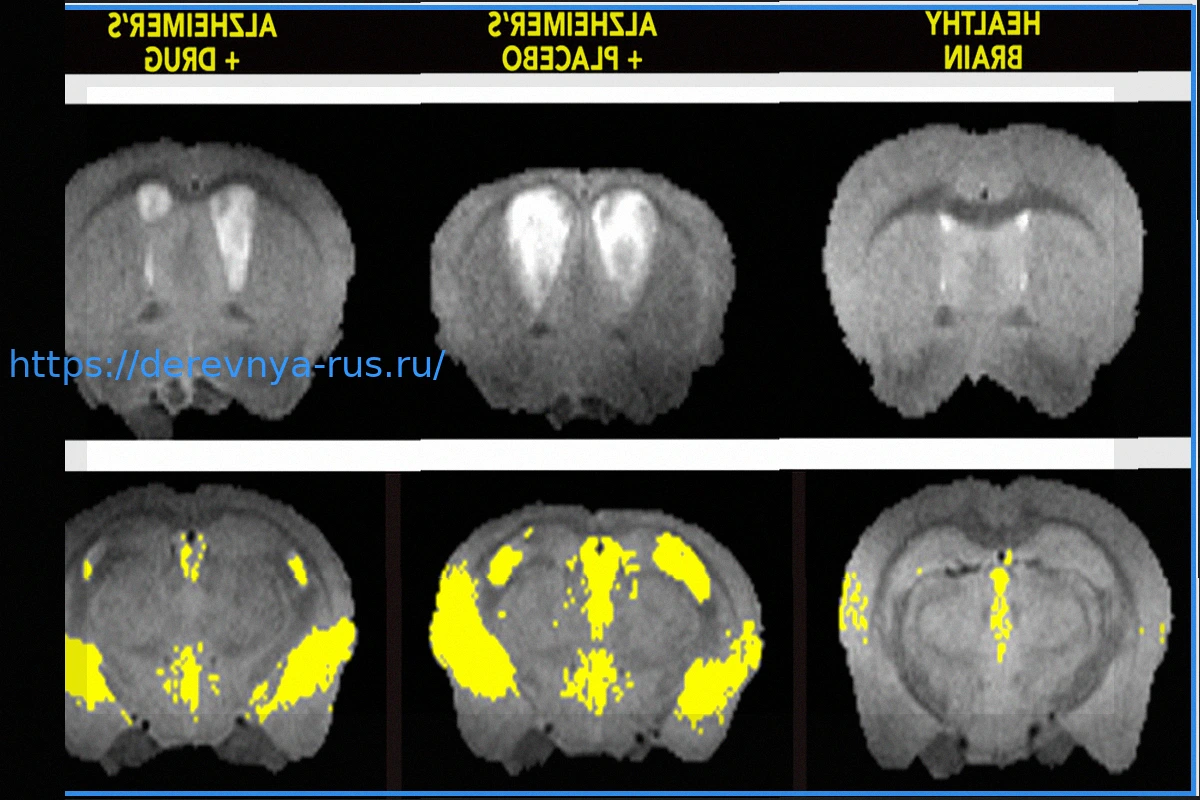

Ученые раскрыли существование скрытого «выключателя смерти» в мозге, который, по всей видимости, является ключевым фактором развития болезни Альцгеймера. Более того, им удалось экспериментально отключить этот механизм у мышей. Основной виновник — токсичное сочетание двух белков, которое при взаимодействии запускает деградацию клеток мозга и значительно усугубляет потерю памяти. Применив новое соединение для разъединения этого смертоносного дуэта, исследователи добились замедления прогрессирования заболевания, защиты мозговых клеток и даже уменьшения характерного накопления амилоидных бляшек.